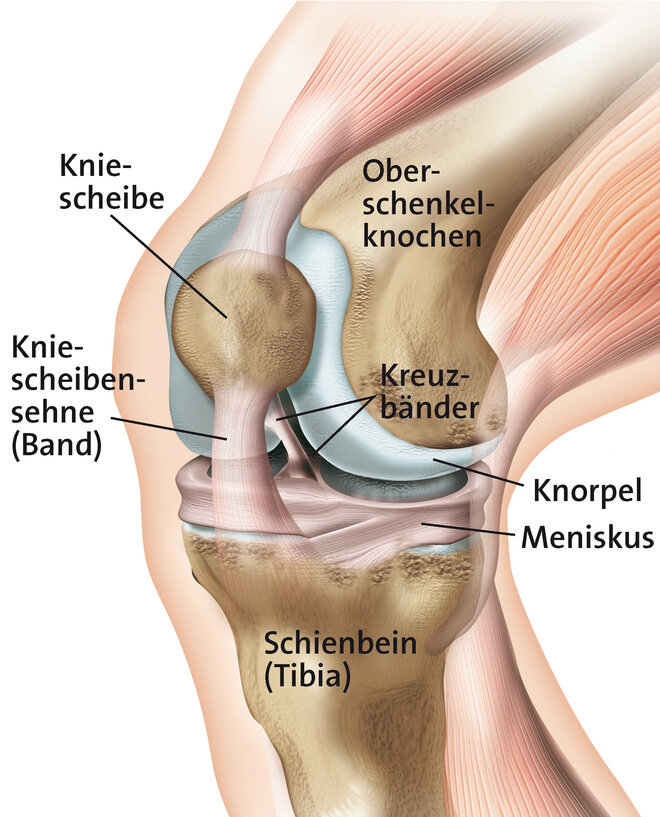

Durch Überbelastung der Kniescheibensehne (Patellarsehne) kommt es an ihrem Ursprung am Unterrand der Kniescheibe zu kleinsten Verletzungen und Auffaserungen der Sehne. In der Nähe bildet sich neues Bindegewebe, Nerven und Blutgefäße sprießen ein. Ärzte sprechen auch von degenerativen Veränderungen. Der allgemeine Fachbegriff ist Tendinopathie (= Sehnenleiden). Zu einer Überlastung der Patellarsehne kommt es vor allem durch sportliche Aktivität, insbesondere bei sogenannten Schnellkraft-Sportarten mit raschen Richtungswechseln, abruptem Abbremsen ("stop and go") und starker Belastung beim Springen und Landen wie beispielsweise Volleyball oder Handball. Daher auch der Begriff Springerknie (englisch: jumpers knee). Betroffen können ein oder beide Knie sein. Meist ist die Sehne am unteren Pol der Kniescheibe betroffen (Insertionstendinose).

Tendinopathien, also Schmerzen an den Sehnen können an verschiedenen Stellen auftreten. Beim Jumpers-Knee handelt es sich um eine Entzündung am Ansatz der Sehne (Insertionstendinose) am unteren Pol der Kniescheibe. Diese tritt vor allem beim sportlichen Erwachsenen auf. Treten die Beschwerden bereits beim Jugendlichen auf handelt es sich meist um einen Morbus Sinding-Larson-Johansen. Auch hierbei kommt es durch Überbelastung zu einer Entzündung am Ursprung der Patellarsehne, bei welcher aber ein Teil der Kniescheibe mitabsterben kann (Osteonekrose).

Hintergrundinformation - Das Kniegelenk